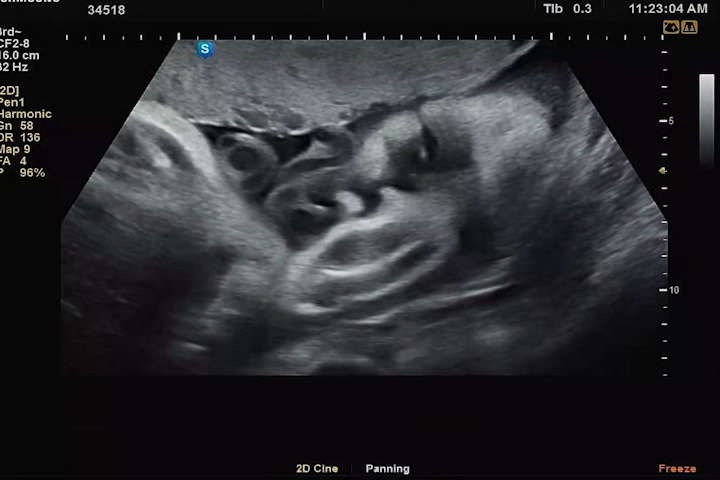

초음파 영상을 보면 까꿍이가 계속 눈을 뜨고 있는 것을 볼 수 있다. 원장샘 말로는 눈 꽤나 오랫동안 뜨고 잘 놀고 있다고 하셨다. 덕분에 장모님도 까꿍이의 모습에 더욱더 생동감을 느끼고 교감하였다고 했다.

두 손으로 얼굴을 가리고 있어서 얼굴 윤곽이 또렷이 나오진 않았지만, 그래도 눈 뜨고 하품도 하고 해서 너무나 귀여웠다. 이전 기록과 비슷하게 주수에 비해 머리둘레는 살짝 크고, 배 둘레, 다리 길이, 체중은 살짝 미달이었다. 체중도 1.8kg 평균주수 대비 살짝 적지만 작은 아가로 태어날거라 생각한다. 그래도 까꿍이 3kg는 찍자꾸나! 화이팅!!!!

우리 까꿍이 하품 큼지막하게 하는 움짤 저장🧡💖 초음파 검사 이후, 태동검사도 하였다.